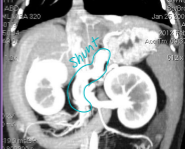

Liver Shunts

Et: genetic (single), acquired multiple (portal hypertension, cirrhosis)

Often seen with microvascular dysplasia, toxins circle systematically (ammonia)

Sig:

Single Congenital: toy breeds (Extrahepatic), Himalayans (Ex), → most common

Lg breeds (Intrahepatic)

Acquired multiple: older Lg breeds, cats

Cs: seizures, head pressing, dull mentation, post-prandial dullness, copper-colored irises(cats), straining, ammonium biurate stones

Dt: low BUN/cholesterol/albumin; high liver enzymes and bile acids; US, CT

Tx: Clavamox, lactulose, low protein diet, Keppra, Sx attenuation (ameroid ring, cellophane band)

Min. 2w medical tx even pre-Sx

Risk of portal hypertension, portal atresia w/ Sx